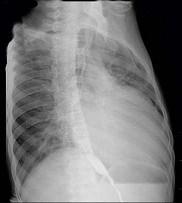

问题 56岁男性患者,劳累后心慌气促10余年,近来自觉症状加重。临床听诊,心尖区有舒张期隆隆样杂音,行胸部X检查,如图所示,你认为下列描述正确的是 ( )

选项 A、考虑三尖瓣狭窄 B、考虑二尖瓣狭窄 C、心后上缘后突压迫冲钡食管 D、左前斜位示心影向后下方突出 E、右前斜位示左心房增大

答案 BCDE